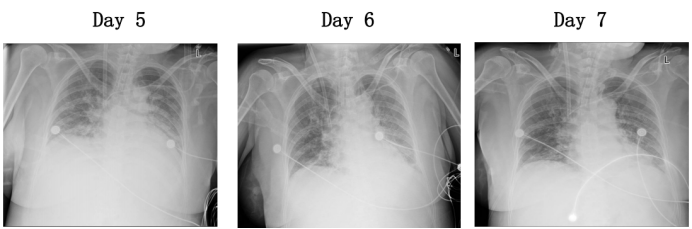

影像学检查显示,患者肺部病变逐渐吸收,出院前复查肺部CT提示肺部浸润影基本消退(图6)。患者住院期间度过除夕及元宵,经过规范治疗后顺利出院,出院后复查肺部情况持续好转(图7),多器官功能恢复正常。

图片

图7  患者院内及出院后胸部CT比较